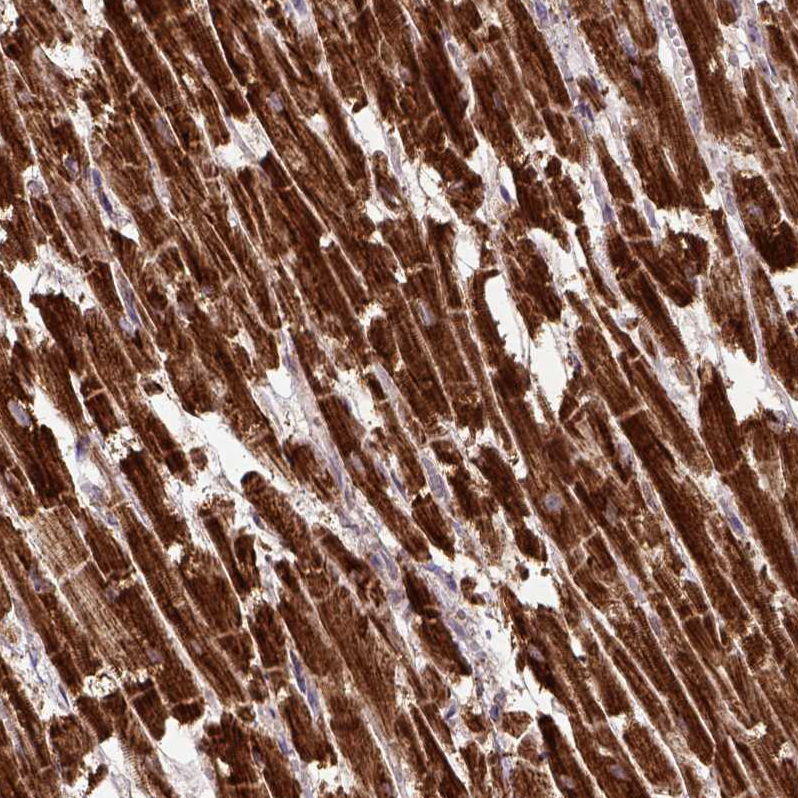

Immunohistochemical staining of human cerebral cortex shows positivity in neurons.